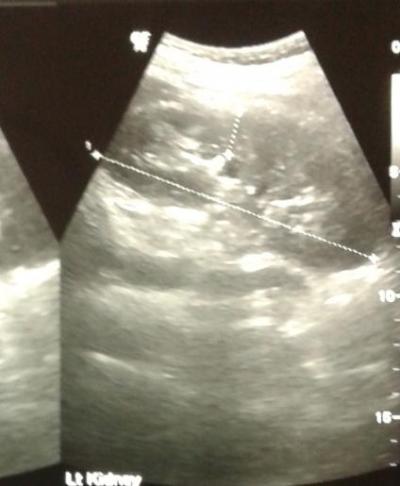

Figure 1: USG revealed a dilated proximal CBD and right intra-hepatic ducts with tubular hyper-echoic structure and mild splenomegaly.